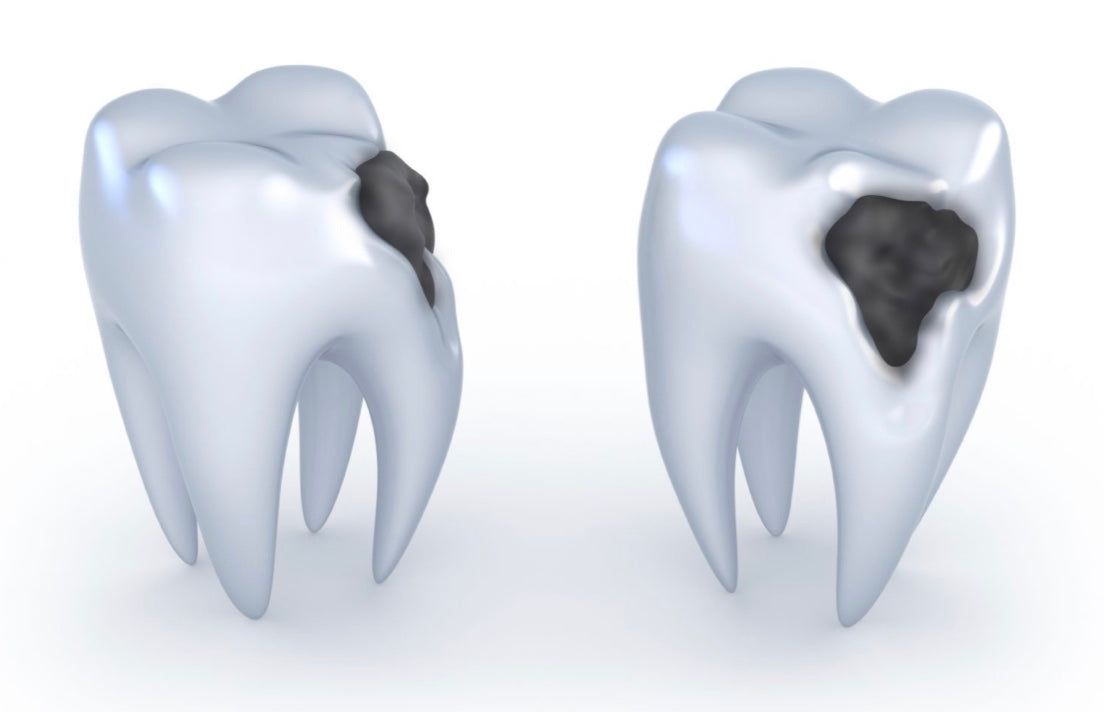

Une carie est une anomalie infectieuse qui se forme dans la dent. Elle cause une lésion de l’émail, de la dentine ou du cément. La carie se développe suite à un déséquilibre de la flore bactérienne buccale.